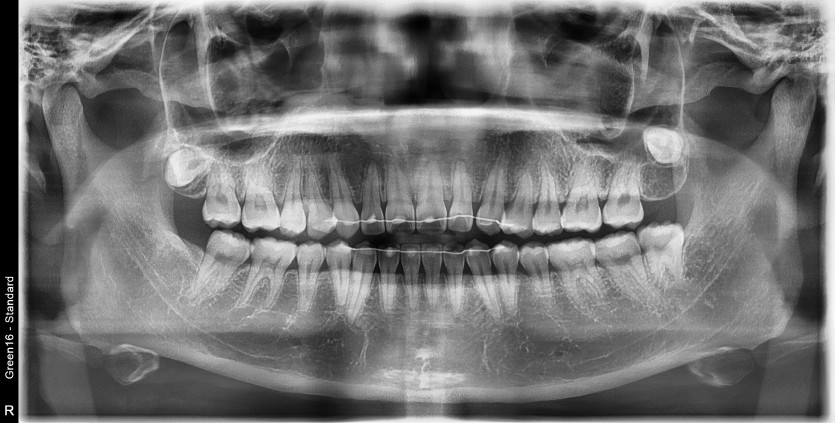

#38 사랑니 발치

구강 외과 전문의가 당일 발치했습니다.